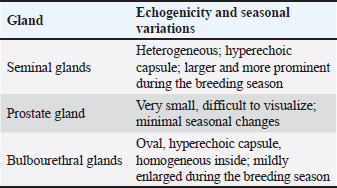

The sex glands of the rats were evaluated ultrasonographically, and the results declared seasonal fluctuations. Higher secretory activity was reflected in the seminal gland by enhanced echogenicity, more lobulated appearance, and clearly defined margins (heterogenous appearance) throughout the breeding season (Fig. 1E; Table 4). Additionally, compared with the nonbreeding phase, the prostate and bulbourethral glands had a denser echotexture and were marginally more noticeable (Fig. 1G–J). The glands seemed smaller, less distinct, and had a more uniform and diminished echogenic pattern during the non-breeding season as a result of lower functional activity (Fig. 1F). Table 4. Seasonal variation in the echogenicity of the glands.